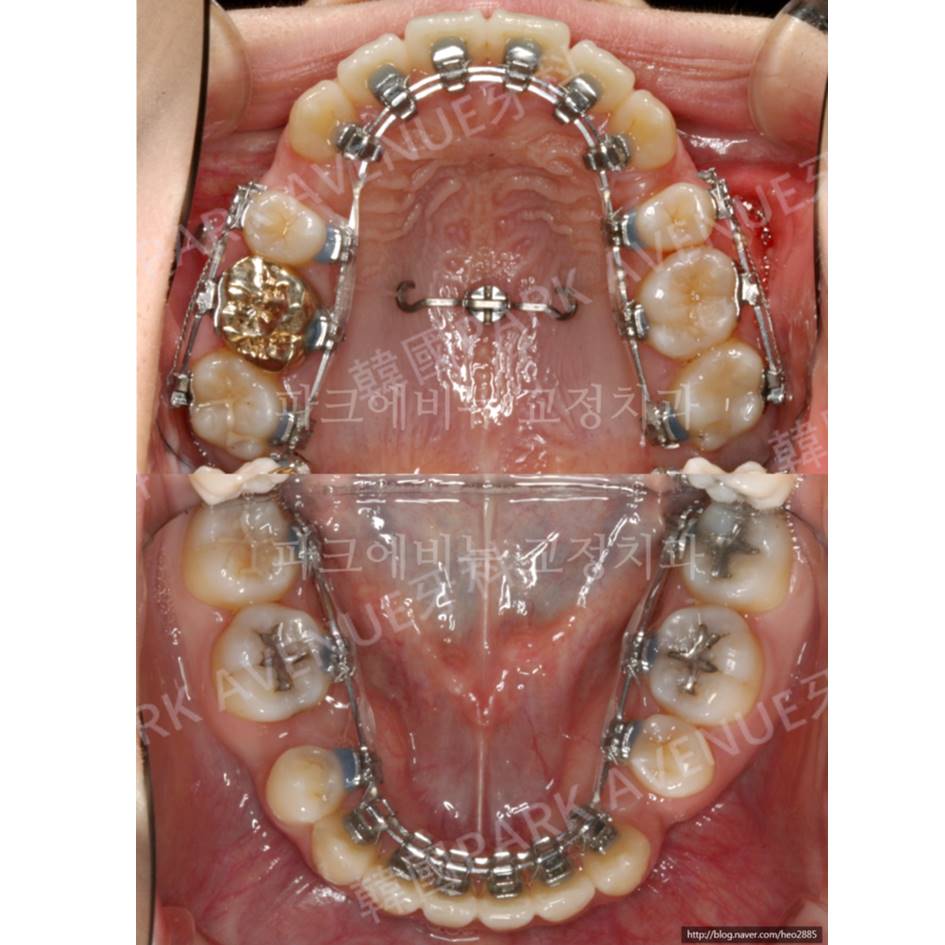

<治疗中>

每次学会被称赞的治疗技术!

采用HEOsystem矫正治疗之一

Lingual bidimensional technique 门牙移动到后面

舌侧的两条钢丝是刻心秘方。;^)

<上颚牙齿的上方移动>

为了无下巴和牙龈露出同时矫正

全体上牙要拉上来。使用三个超小型螺丝上颚牙齿拉上来了。

为了无下巴和牙龈露出同时矫正

全体上牙要拉上来。使用三个超小型螺丝上颚牙齿拉上来了。

有时候也有种8个超小型螺丝的矫正牙医也有,

但是好好设计离奇的方向,

使用小数量的超小型螺丝也

万分可以的。